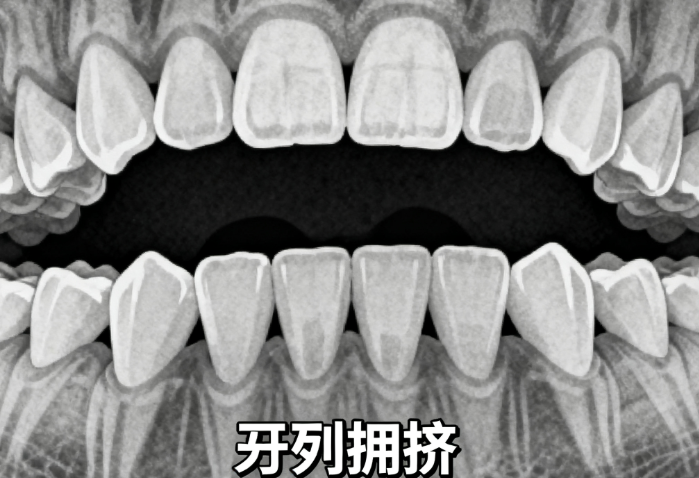

二、正畸矫正项目价格区间

1、传统钢牙套矫正

¥5000–15000

价格差异主要来自品牌、医生经验、矫正周期长短。

2、隐形矫正(如Invisalign)

¥15000–30000

这类矫正更隐蔽,材料成本高,适合对外观要求高的人群。

3、儿童早期矫正

¥2000–8000

价格相对较低,但需根据孩子年龄和牙齿发育情况定制方案。